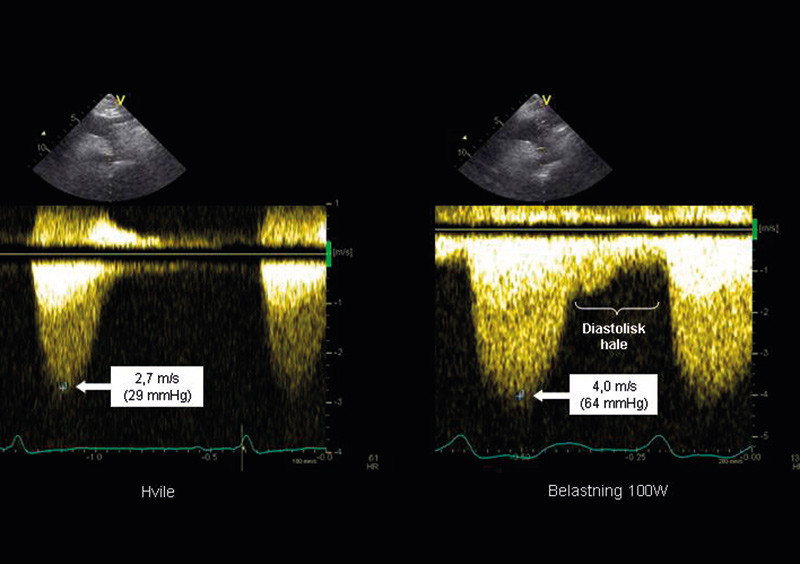

Recoarctation can be estimated with echocardiography, and a pressure drop of > 20 – 30 mmHg at rest is suggested as a threshold for intervention (36). In case of a lower pressure drop, ergometric stress echocardiography can be used to determine the significance of the residual stenosis during physical exercise. In this context, 50 mmHg is used as a flexible limit. However, it is equally important to assess whether there is a «diastolic tail» (Figure 4) (37), which may indicate a haemodynamic significance of the (re-)coarctation.

Figure 4:  Echo recordings from a patient referred for a possible recoractation after a previous operation for coarctation…

Figure 4: Echo recordings from a patient referred for a possible recoractation after a previous operation for coarctation. The images demonstrate continuous Doppler recordings from the descending part of the aortic arc. On the left, we see recordings at rest with a peak velocity of 2.7 m/s and an estimated pressure drop of 29 mmHg, on the right we see recordings made during exercise at 100 W, with a velocity increasing to 4.0 m/s, resulting in a pressure drop of 64 mmHg (note the different scales for blood-flow velocity in the two images). Note also the addition of a distinct «diastolic tail».